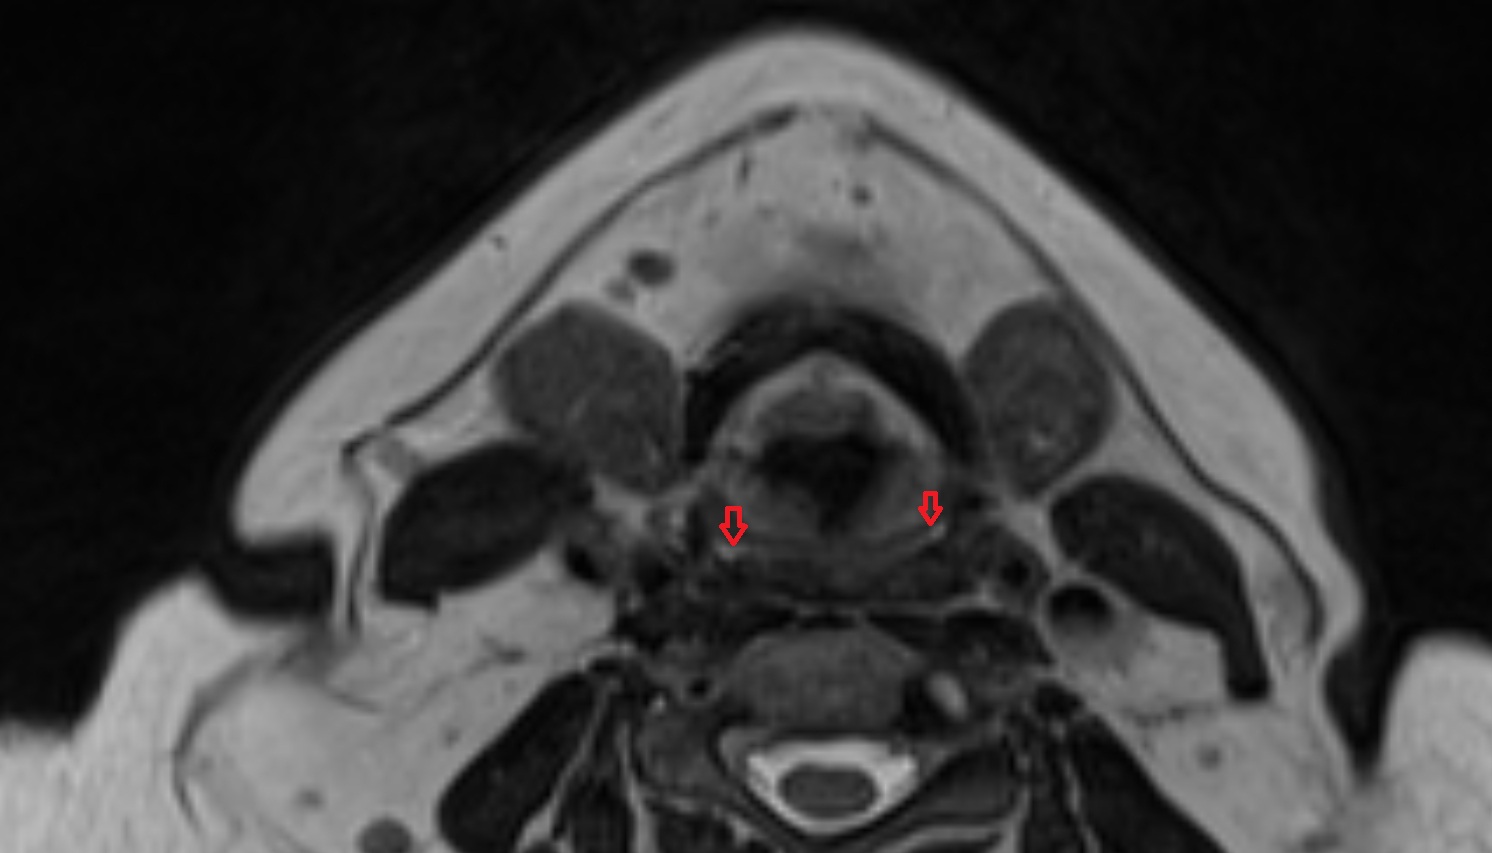

- Superior head of lateral pterygoid muscle

- Inferior head of lateral pterygoid muscle

- Lateral pterygoid muscle